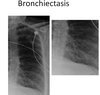

- What can be seen on that X ray? (characteristic feature) (2)

- What’s the diagnosis?

- CT chest showing widespread tram-track and signet ring signs

- diagnosis: bronchiectasis

Characteristic features of CXR in bronchiectasis

- May be normal

- Ring opacities, tram-tracks

- Fluid-filled cysts or bronchocoeles

Characteristic features of CT in bronchiectasis

- Signet ring sign and tram-tracks

- Lack of tapering of airways - thickness is NOT reduced towards the end

- Mucus impaction

- Mosaicism (vessels of different size in different regions of the lungs - smaller where less perfused)